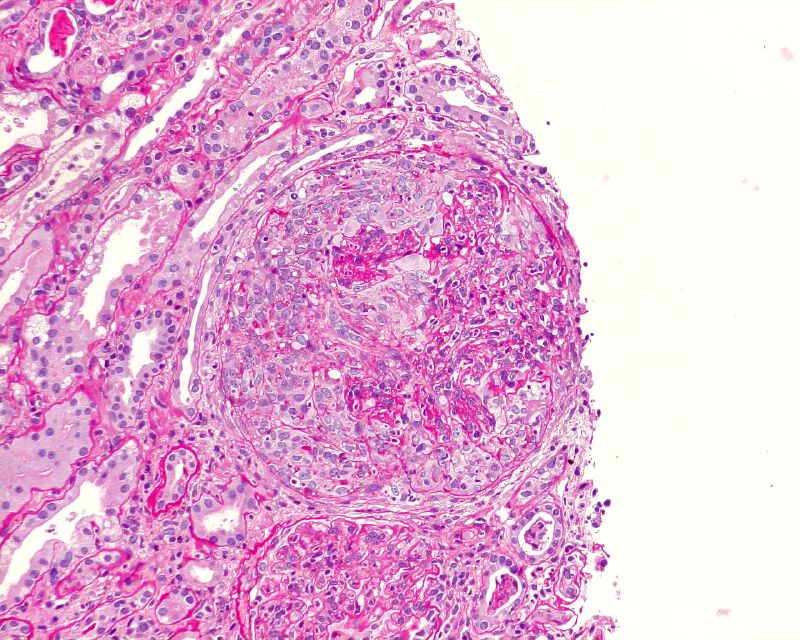

Renal biopsies on the other hand are only 60 years old; but the development of immunofluorescence and electron microscopy in the 1960s led to a flowering of disease descriptions and understanding – and occasionally, treatments.

![]() |

| Renal biopsy |

The invention of the renal biopsy

Dipsticks – tool for the world, and invaluable in identifying kidney disease. Biopsies – for characterising it; can you imagine nephrology without it?

So, which was more important to nephrology and the world? Read more at the AJKD Nephmadness blog. Then vote (hover over titles for more info).